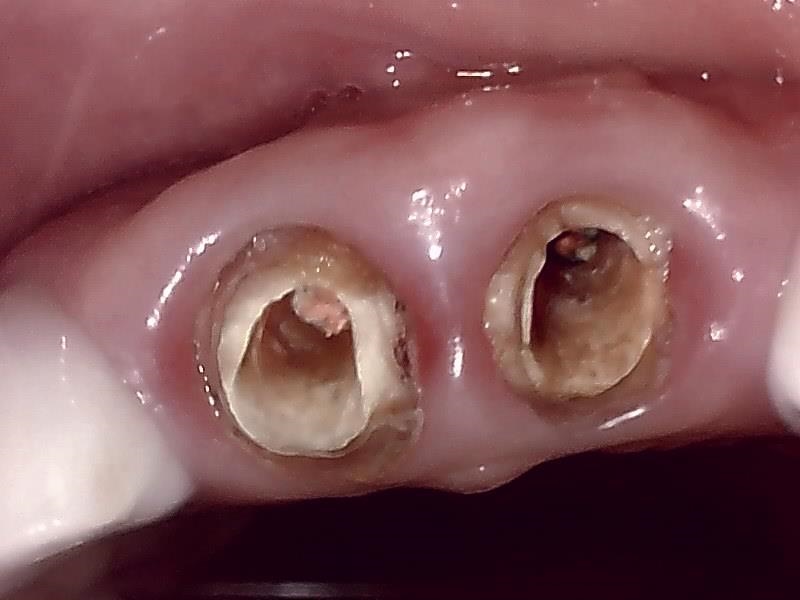

抜歯前の状態

虫歯や歯の破折によって保存が難しくなった前歯。大きく崩壊しており、審美的にも機能的にも改善が必要な状態です。